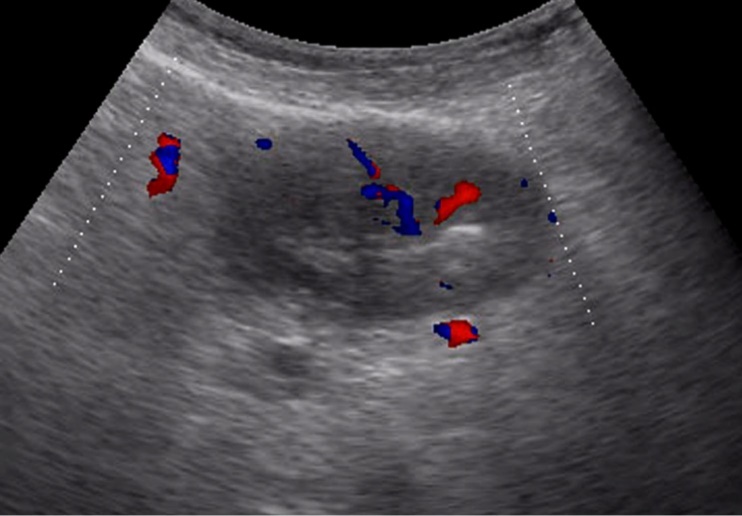

Weak vascularization was manifested in the form of a single point color vascular signals, the moderate vascularization - in the form of linear color vascular signals and the enhanced vascularization - in the form of wide color areas inside the tumor (Figure 16, Figure 17).

Figure 17.Gastric carcinomas of infiltrative ulcerative form of Ts stage. Despite the small size of the tumor the vascularization is manifested in the form of wide color areas inside the tumor.